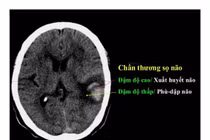

(khoahocdoisong.vn) - Chấn thương sọ não nặng được điều trị bằng phẫu thuật, hồi sức hoặc phối hợp. Kết quả hồi sức và điều trị bệnh nhân chấn thương sọ não nặng phụ thuộc vào nhiều yếu tố như tuổi, tình trạng bệnh nhân, tổn thương tại não, tổn thương phối hợp, thời điểm điều trị.

(khoahocdoisong.vn) - Chấn thương sọ não thường bắt nguồn từ các loại chấn thương về não bao gồm chảy máu, chấn động mạnh, rung động não hoặc não bị bầm.